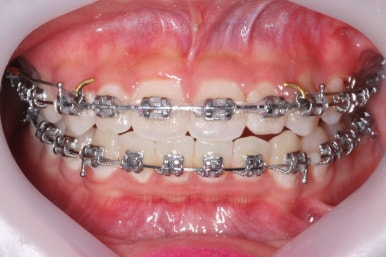

마무리 때의 모습입니다.

치아는 매우 가지런해졌고 뾰족하던 앞니의 형태도 좋아졌어요.

매복되어 있던 송곳니도 잘 나왔고 과개교합도 물론 개선이 되었습니다.

대신 웃거나 말하는 모습에서 드러나는 치열은 매우 예뻐졌어요.

부산교정치과 키다리아저씨치과에서 치료한 이번 치료의 전후사진을 비교해 볼게요.

왼쪽이 치료 전, 오른쪽이 치료 후 모습입니다.

매우 복잡한 문제들을 복합적으로 가지고 있었던 경우였지만 만족할만한 결과를 얻을 수 있었어요.